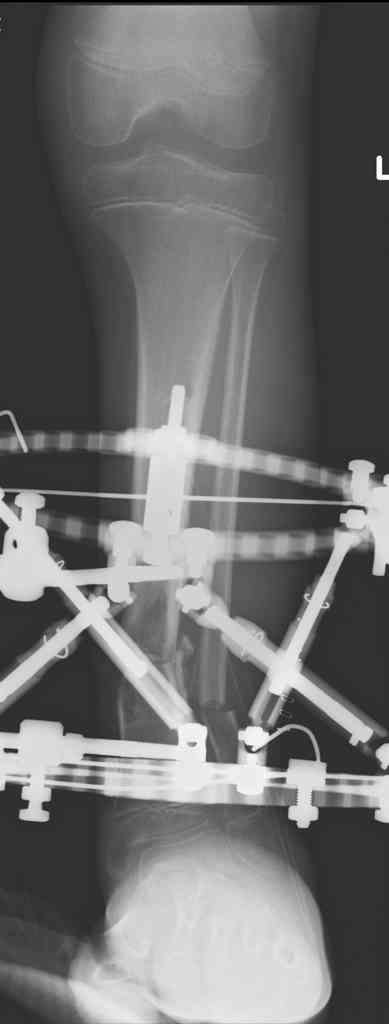

Another choice is simply perform shortening + posterior angulation with Ilizarov or TSF , than gradual correction of the angulation.After all apply third ring on the proximal tibia and start lengthening.

We had recently similar case in 14 years old boy with 45 mm bone defect after open tibial fracture.Boy doing excellent .This technique is not new, Sasha Lerner did it in Rambam , Rozbruch wrote also.

Another advantage of this techniqe is relaxation of soft tissue and possibility for closure even large defects of the skin.In your case I will apply ring on the foot and mid diaphysis of the tibia ,removal of the fibular plate,sindesmotic wire, and after correction of angulation on the proximal tibia.

Действительно, если есть длинная косая линия на проксимальном отломке, это жалко будет не использовать. Можно сделать коррекцию угла не обратным разведением фрагментов, а оставить их в контакте, и сделать кортикотомию проксимальнее на 2-3 см. Можно и сейчас отсечь такой фрагмент и транспортировать его с разворотом. Наверно, вариант с ангуляцией более технологичен.

Да, надо удалить все железо, сделать для ангуляции остеотомию малоберцовой на уровне дефеормации, а после восстановления оси сразу освободить стопу. То есть в дистальном отломке tibia надо побольше

спиц с упорами, а на диафизе только half-pins с передне-внутренней стороны, чтобы как можно меньше пострадала передняя группа мышц.